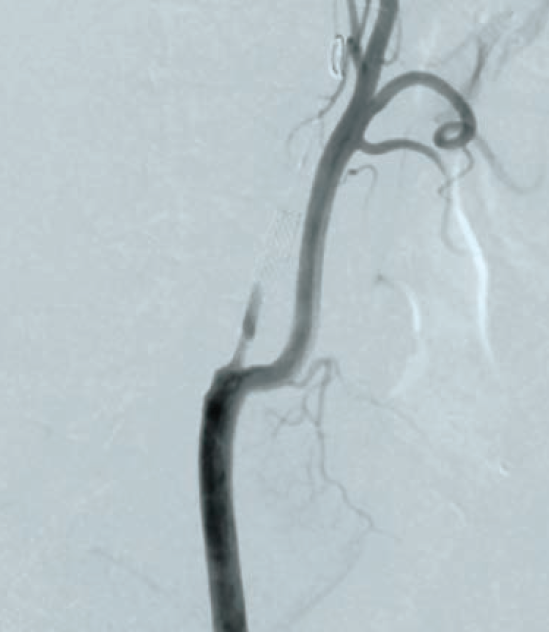

Following aseptic measures and under local anesthesia, a 7 French (Fr) right femoral access was obtained using a routine-length sheath. An .035-inch J-tip guide wire was then parked at the right common carotid artery (RCCA) using a 5 Fr Judkins right catheter, exchanged by a 7 Fr multipurpose guide. This was followed by advancement of a FilterWire EZ (Boston Scientific) across the ostial internal carotid artery stenosis, and deployed in the distal part of the extracranial ICA (Figure 2). After deployment of the FilterWire EZ, a direct stenting strategy was adopted to minimize thromboembolization. A 6 mm x 40 mm self-expanding stent was deployed at the RICA ostium (Figure 3). To our surprise, the view after stent placement showed zero flow into the distal RICA. (Figure 4) The reason appeared to be choking of the filter due to thromboembolization. The filter appeared to be overwhelmed by the volume of the debris captured. A 6 Fr Export catheter (Medtronic) was employed to suction debris from the distal ICA (Figure 5). We also administered pharmacotherapy using intra-arterial nitrate boluses and a weight-based tirofiban bolus. After these measures, there was fair flow into the distal ICA. During the period of no flow, the patient had transient hemispheric ischemic signs and an oropharyngeal airway was required, but his vitals remained stable. These symptoms rapidly resolved after establishment of ICA flow. After establishing blood flow, the proximal half of the stent that remained under-expanded was post dilated using a 4.5 mm noncompliant balloon at 12 atmospheres (Figure 6). Post dilatation, the angiographic view demonstrated good stent expansion and adequate distal flow (Figure 7). The distal protection device was then successfully removed using its retrieval sheath. The final DSA angiogram revealed excellent flow into the distal carotid (Figure 8A) and intracranial vasculature (Figure 8B), confirming no intracranial embolization. The guide was then safely removed over the .035-inch guide wire.